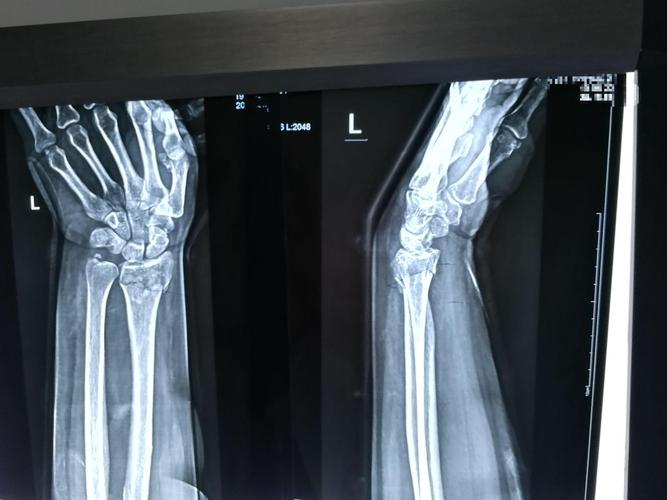

右手手腕骨裂图片

右手手腕骨裂图片,手腕骨折的真实图片

手腕三角骨折了

桡骨远端粉碎性骨折,一定要手术吗?

李医生好,情况是这样子的,我朋友前几天出了场小车祸,右手手腕骨折

点,局部压痛明显,可触及骨擦音及骨右腕关节活动受限,右手各手指感

桡骨远端骨折病人一定要手术治疗吗

手腕骨折的真实图片

手腕骨裂

手腕骨断裂图片

骨裂的片子图片